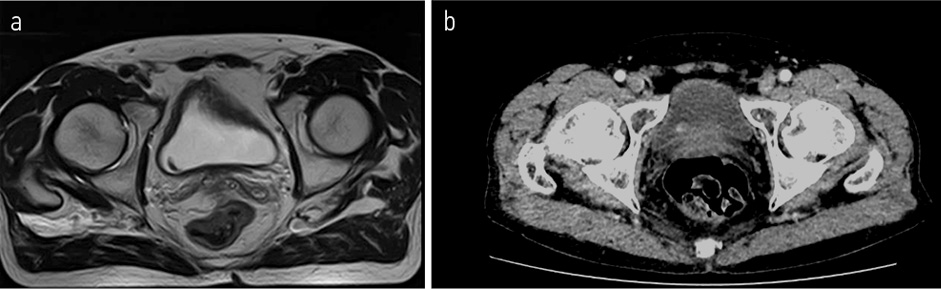

С 08.2022 начал получать полихимиотерапию (ПХТ) по схеме: карбоплатин + иринотекан. По данным контрольного обследования 18.08.2022 отрицательная динамика в виде увеличения размеров метастатических очагов в костях таза, наибольшими размерами в левой подвздошной кости на уровне тазобедренного сустава до 25×23 мм (ранее до 17×15 мм), в крыле правой подвздошной кости до 36×18 мм (ранее до 15×7 мм), в боковой массе крестца слева до 24×26 мм (ранее до 18×14 мм); рис. 8. Обсужден на консилиуме №91016 от 09.11.2022, рекомендовано: проведение паллиативной лучевой терапии последовательно на область правой и левой половины таза в разовой очаговой дозе (РОД) 6,5 Гр до суммарной очаговой дозы (СОД) 26 Гр.

Рис. 8. МРТ ОМТ от 18.08.2022 в сравнении КТ ОМТ от 02.11.2022. Состояние после 3 курсов лекарственного лечения по схеме карбоплатин + иринотекан.

Fig. 8. Pelvic MRI dated 18.08.2022 in comparison with pelvic CT dated 02.11.2022. State after 3 courses of drug treatment with carboplatin + irinotecan.

С 08.2022 по 22.12.2022 проведено 6 курсов лекарственного лечения по схеме карбоплатин + иринотекан. По результатам контрольного обследования от 01.2023: отрицательная динамика в виде увеличения размера очагов в костях скелета: в левой подвздошной кости до 29×25 мм (ранее до 25×23 мм) и 38×26 мм (ранее до 33×25 мм), в крыле подвздошной кости до 56×19 мм (ранее 27×22 мм), в боковой массе крестца слева до 28×23 мм (ранее 27×22 мм) и появления новых мелких очагов в бедренных костях до 5 мм и в телах LII–IV позвонков диаметром до 3 мм; билобарного очагового поражения печени: в S2 – до 20×23 см, на границе S2|3 – до 13×15 см, в S6 – 8×11 мм (рис. 9, 10).